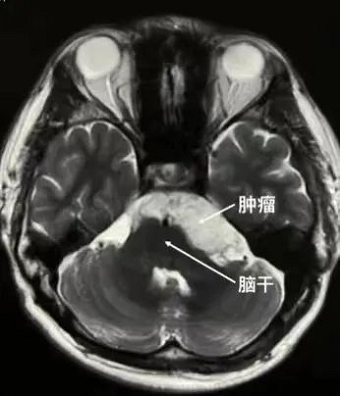

医生告诉他头痛的原因是脑内长东西了——颅内胆脂瘤(珍珠瘤)。虽然临床上,大多数表皮样囊肿是良性病变,但通过头颅磁共振检查发现,在陈先生桥脑小脑角区、桥前池、环池的肿瘤长约6cm,局部脑干及小脑明显受压,如不能及时解除压迫,随着肿瘤不断增长,将会对周围神经系统形成不可逆性损伤,遗留持久性功能障碍。

手术开始!冯恩山主任先沿着耳后直切口,逐层切开头皮、肌肉,暴露颅骨,然后使用高速动力系统,磨钻钻孔,铣刀铣下大小约4cmx4cm的骨瓣,控制导静脉的出血,这时就要使用显微镜了,显微镜下冯恩山主任小心剪开硬脑膜,充分释放脑脊液,以降低小脑对肿瘤的阻挡,随后牵开小脑,“漂亮”的肿瘤就出现在眼前,肿瘤呈乳白色,在显微镜灯光的照耀下显得晶莹剔透,宛如珍珠一样。

在十余年的生长过程中,几乎所有的神经和血管间隙里都长满了肿瘤,这时就要非常仔细地从各个角度将肿瘤分块切除,肿瘤位于脑干的前方,稍有不慎,就有可能导致呼吸心跳的改变,肿瘤因为生长较大,有一部分肿瘤从左侧跨过中线长到了右侧,导致一部分肿瘤“死角”无法使用显微镜观察到,这是神经内镜就派上了用场,从已有的手术通道置入内镜系统,在内镜下,所有藏在死角的肿瘤也无处可逃,都被一点一点地移除。电生理监测提示各支颅神经功能完好。经过3个多小时紧张手术终于顺利切除肿瘤。“这个肿瘤的生长特点给全切带来难度,”谈及手术的难度,冯恩山说,让我们感到棘手的第一个手术难点是肿瘤本身的生长特点,它好发于桥小脑角区、鞍上池及第四脑室等,也就是长在脑袋里面脑脊液流动的各种小水沟、小水池里。这个肿瘤特点是质地较软,见缝就钻,所以生长在脑干、血管与神经之间,并且会向对侧生长,还有就是肿瘤的囊皮会与肿瘤粘连较重,增加神经损伤的风险,从而给手术切除带来难度。手术极具风险的第二个难点是,陈先生的肿瘤长在脑小脑角区,桥小脑角区的解剖部位非常复杂,存在丰富的神经血管脑组织结构和神经,三叉神经、外展神经、面听神经、舌咽神经、迷走神经、副神经都从桥小脑角区经过。在切除肿瘤的同时,更要保护好神经、血管,不能有一点儿闪失。术中及时、准确的电生理监测为保护各支神经功能提供了保障。